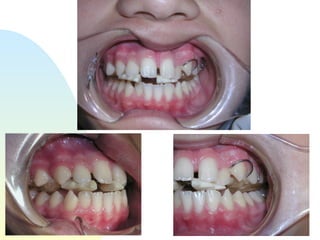

Diastemas created, rounding of arch form, teeth freed up to move

Diastemas created, roundingof arch form, teeth freed up to move

If teeth have room, they’ll move!

If teeth haveroom, they’ll move!